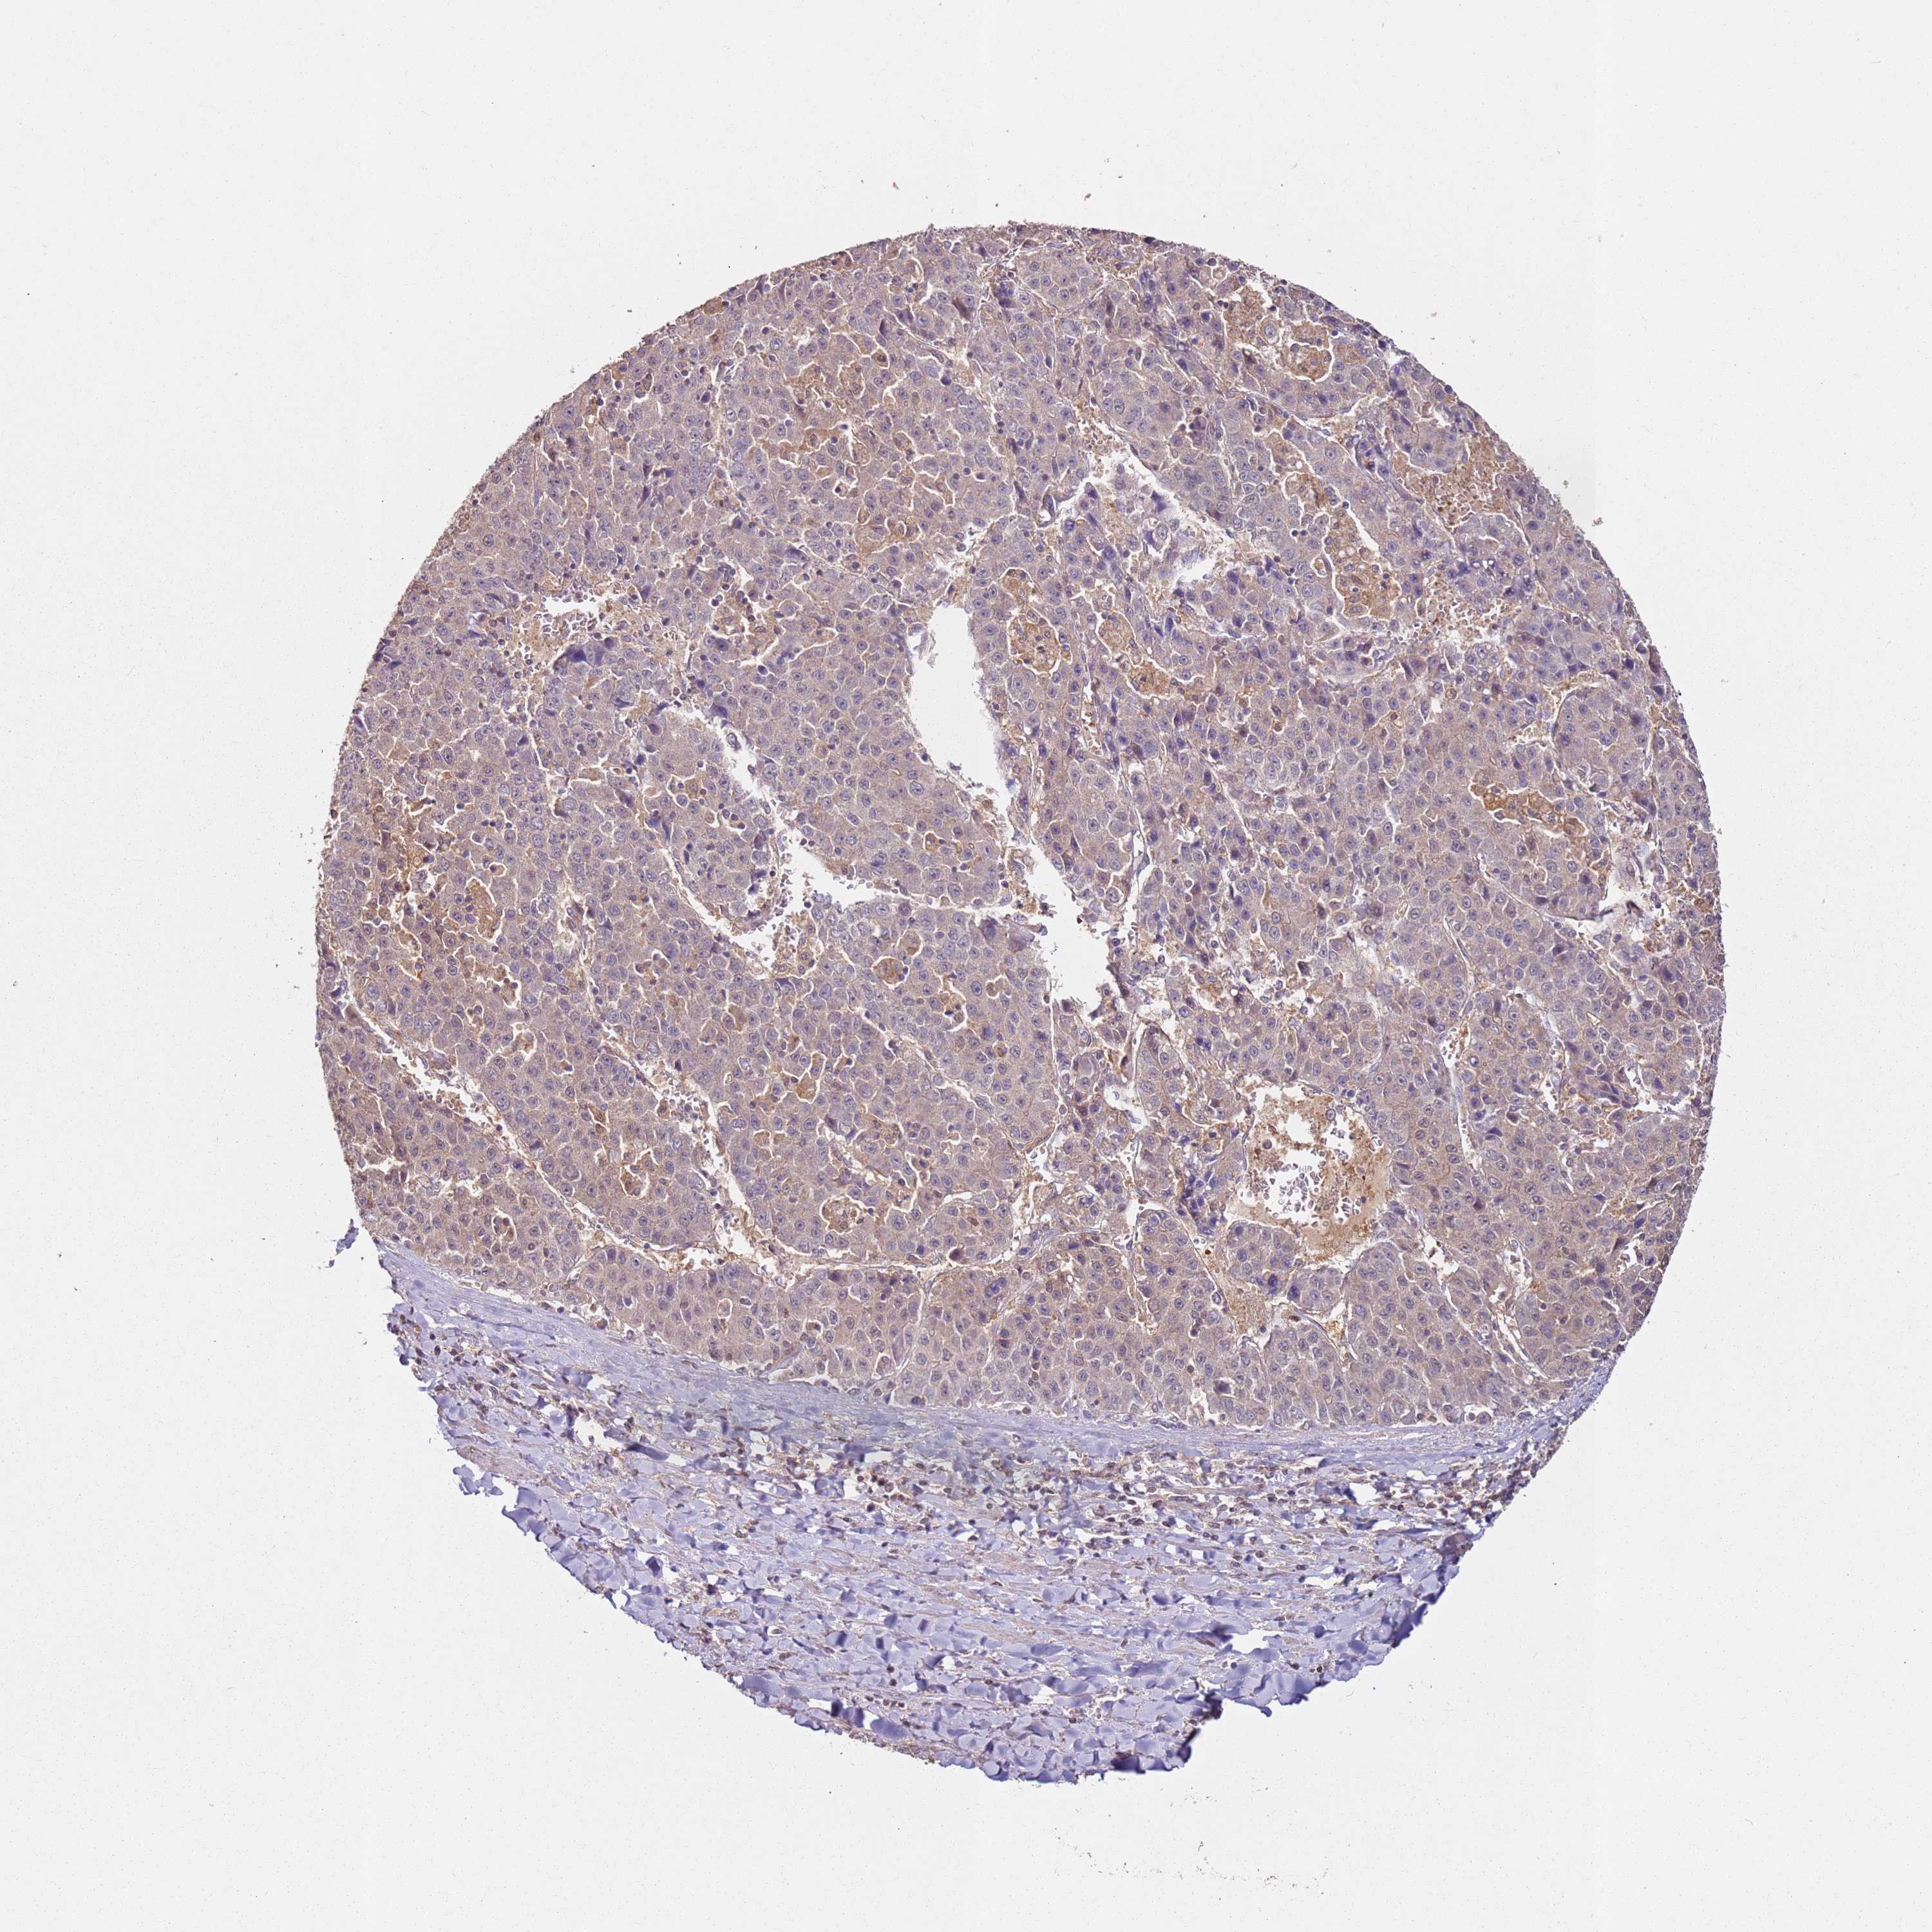

LIVER CANCER - Protein expressioni

A mouse-over function shows sample information and annotation data. Click on an image to view it in a full screen mode. Samples can be filtered based on level of antibody staining by selecting one or several of the following categories: high, medium, low and not detected. The assay and annotation is described here.

Note that samples used for immunohistochemistry by the Human Protein Atlas do not correspond to samples in the TCGA dataset.

Antibody stainingi

Antibody staining in the annotated cell types in the current human tissue is reported as not detected, low, medium, or high, based on conventional immunohistochemistry profiling in selected tissues. This score is based on the combination of the staining intensity and fraction of stained cells.

Each image is clickable and will lead to virtual microscopy that enables deeper exploration of all samples and also displays staining intensity scores, fraction scores and subcellular localization as well as patient and tissue information for each sample.

Antibody HPA027296

Antibody HPA054276

Antibody CAB047333

Staining

High

Medium

Low

Not detected

Intensity

Strong

Moderate

Weak

Negative

Quantity

>75%

75%-25%

<25%

None

Location

Nuclear

Cytoplasmic/membranous

Cytoplasmic/membranous,nuclear

Cholangiocarcinoma

Carcinoma, Hepatocellular, NOS